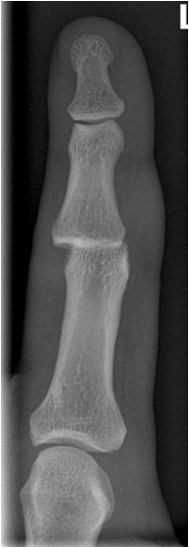

Fig. 14. Typical degenerative changes in the hand: A) Joint space narrowing and subchondral sclerosis of the trapezoidum-scaphoidal joint and the first carpal-metacarpal joint. B.) Degenerative arthritis of the distal interphalangeal joint showing typical osteophyte formation, joint space narrowing and increased sclerosis.